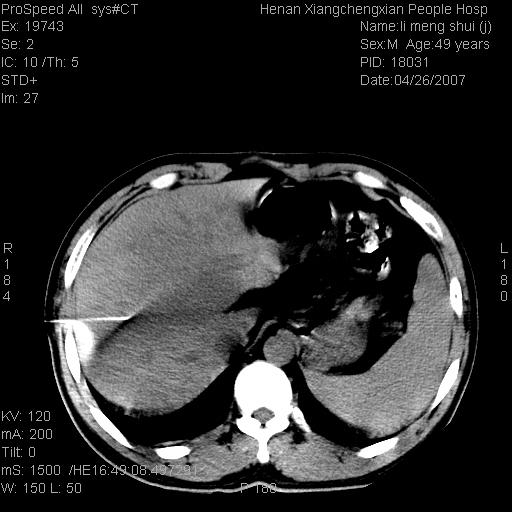

| 患者,男,49岁, 腹疼伴恶心\\呕吐20天,20天前无明显诱因出现右上腹部疼痛,钝疼,无放射,伴恶心\\呕吐,不伴发热.患者不愿增强. b超:肝脏右叶实性占位. ct:肝脏右叶可见一巨块状圆形低密度影,大小约93mm*84mm,其内可见点状高密度影,胆囊、胰腺、脾脏大小、形态及密度未见异常,腹膜后间隙未见肿大淋巴结影。 印象:肝脏右叶巨大肿块,性质待定,建议增强并穿刺活检进一步确诊。 ct平扫: ![]() ![]() ![]() ![]() ![]() ![]() ![]() ![]() ![]() ![]() ![]() ![]() ![]() ![]() ![]() ![]() ![]() 肝脏右叶肿块ct引导下穿刺活检术 患者于16时05分仰卧于ct检查台上,首先行肝脏ct扫描确定进针位置、深度、角度。在局麻下行ct引导下肝脏右叶肿块穿刺活检术。常规消毒、铺巾、局麻。在ct引导下使活检针经右侧腋中线、第9肋间隙垂直胸壁进针90mm,针头进入病变预定位置。在病变预定位置多点、多方向抽取小米样病变组织多块,涂片五张送病理检查。术后穿刺点局部无出血,未出现腹腔积液等并发症。术中及术后患者生命体征稳定,手术于17时10分成功完成。患者安返病房。 穿刺片 ![]() ![]() ![]() ![]() ![]() ![]() ![]() ![]() ![]() ![]() ![]() ![]() ![]() ![]() ![]() ![]() 病理结果肝细胞癌 ![]() 原贴地址:http://www.radinet.com.cn/forum_view.asp?forum_id=4&view_id=24130 ok |